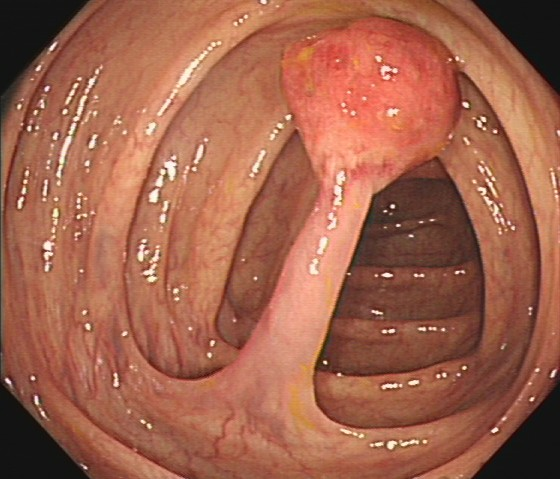

(3)邓先生(54岁,乙状结肠息肉,图3)

肠镜一照,息肉现形!形态各异的大肠息肉,离癌有多远?(图3)

图3

病理诊断:(乙状结肠)管状腺瘤。

解读:这是最常见的腺瘤类型。若未发现高级别瘤变或癌变,属于相对早期的癌前病变。但放任不管,其癌变风险随时间推移而增加。距离癌:潜在风险,癌前病变早期。